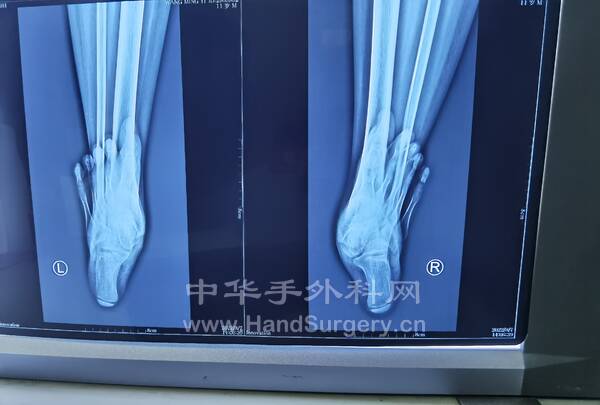

今日门诊女,38岁,距骨脱位,足下垂 诊断:术式:2022-6-29 15:30--19:50

1.跖筋膜松解

2.跟腱延长

3.胫前肌腱松解转位(固定在第三腓骨肌腱)

4.胫后肌腱和踇长伸肌腱松解

5.距下关节融合

6.环形外固定架固定

今日术后38天复查